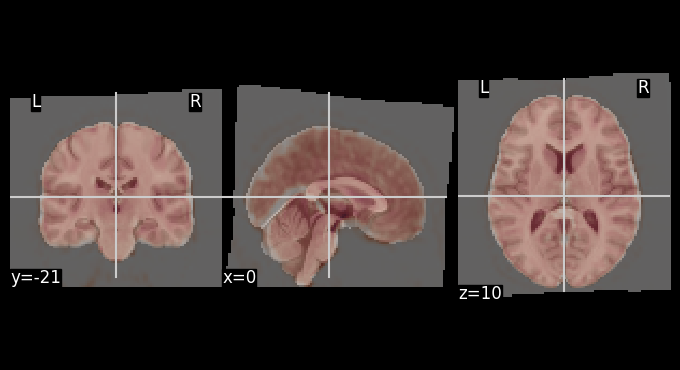

Let’s use add_contours as another visualization option for checking coregistration by overlaying the MNI template as contour (red) on top of mean functional image (background):

# Create a binary mask of the template

template_mask = math_img("img > 0.1", img=template)

display = plotting.plot_anat(mean_bold, title="Edges of MNI template on mean BOLD", colorbar=False)

display.add_contours(template_mask, colors='r')